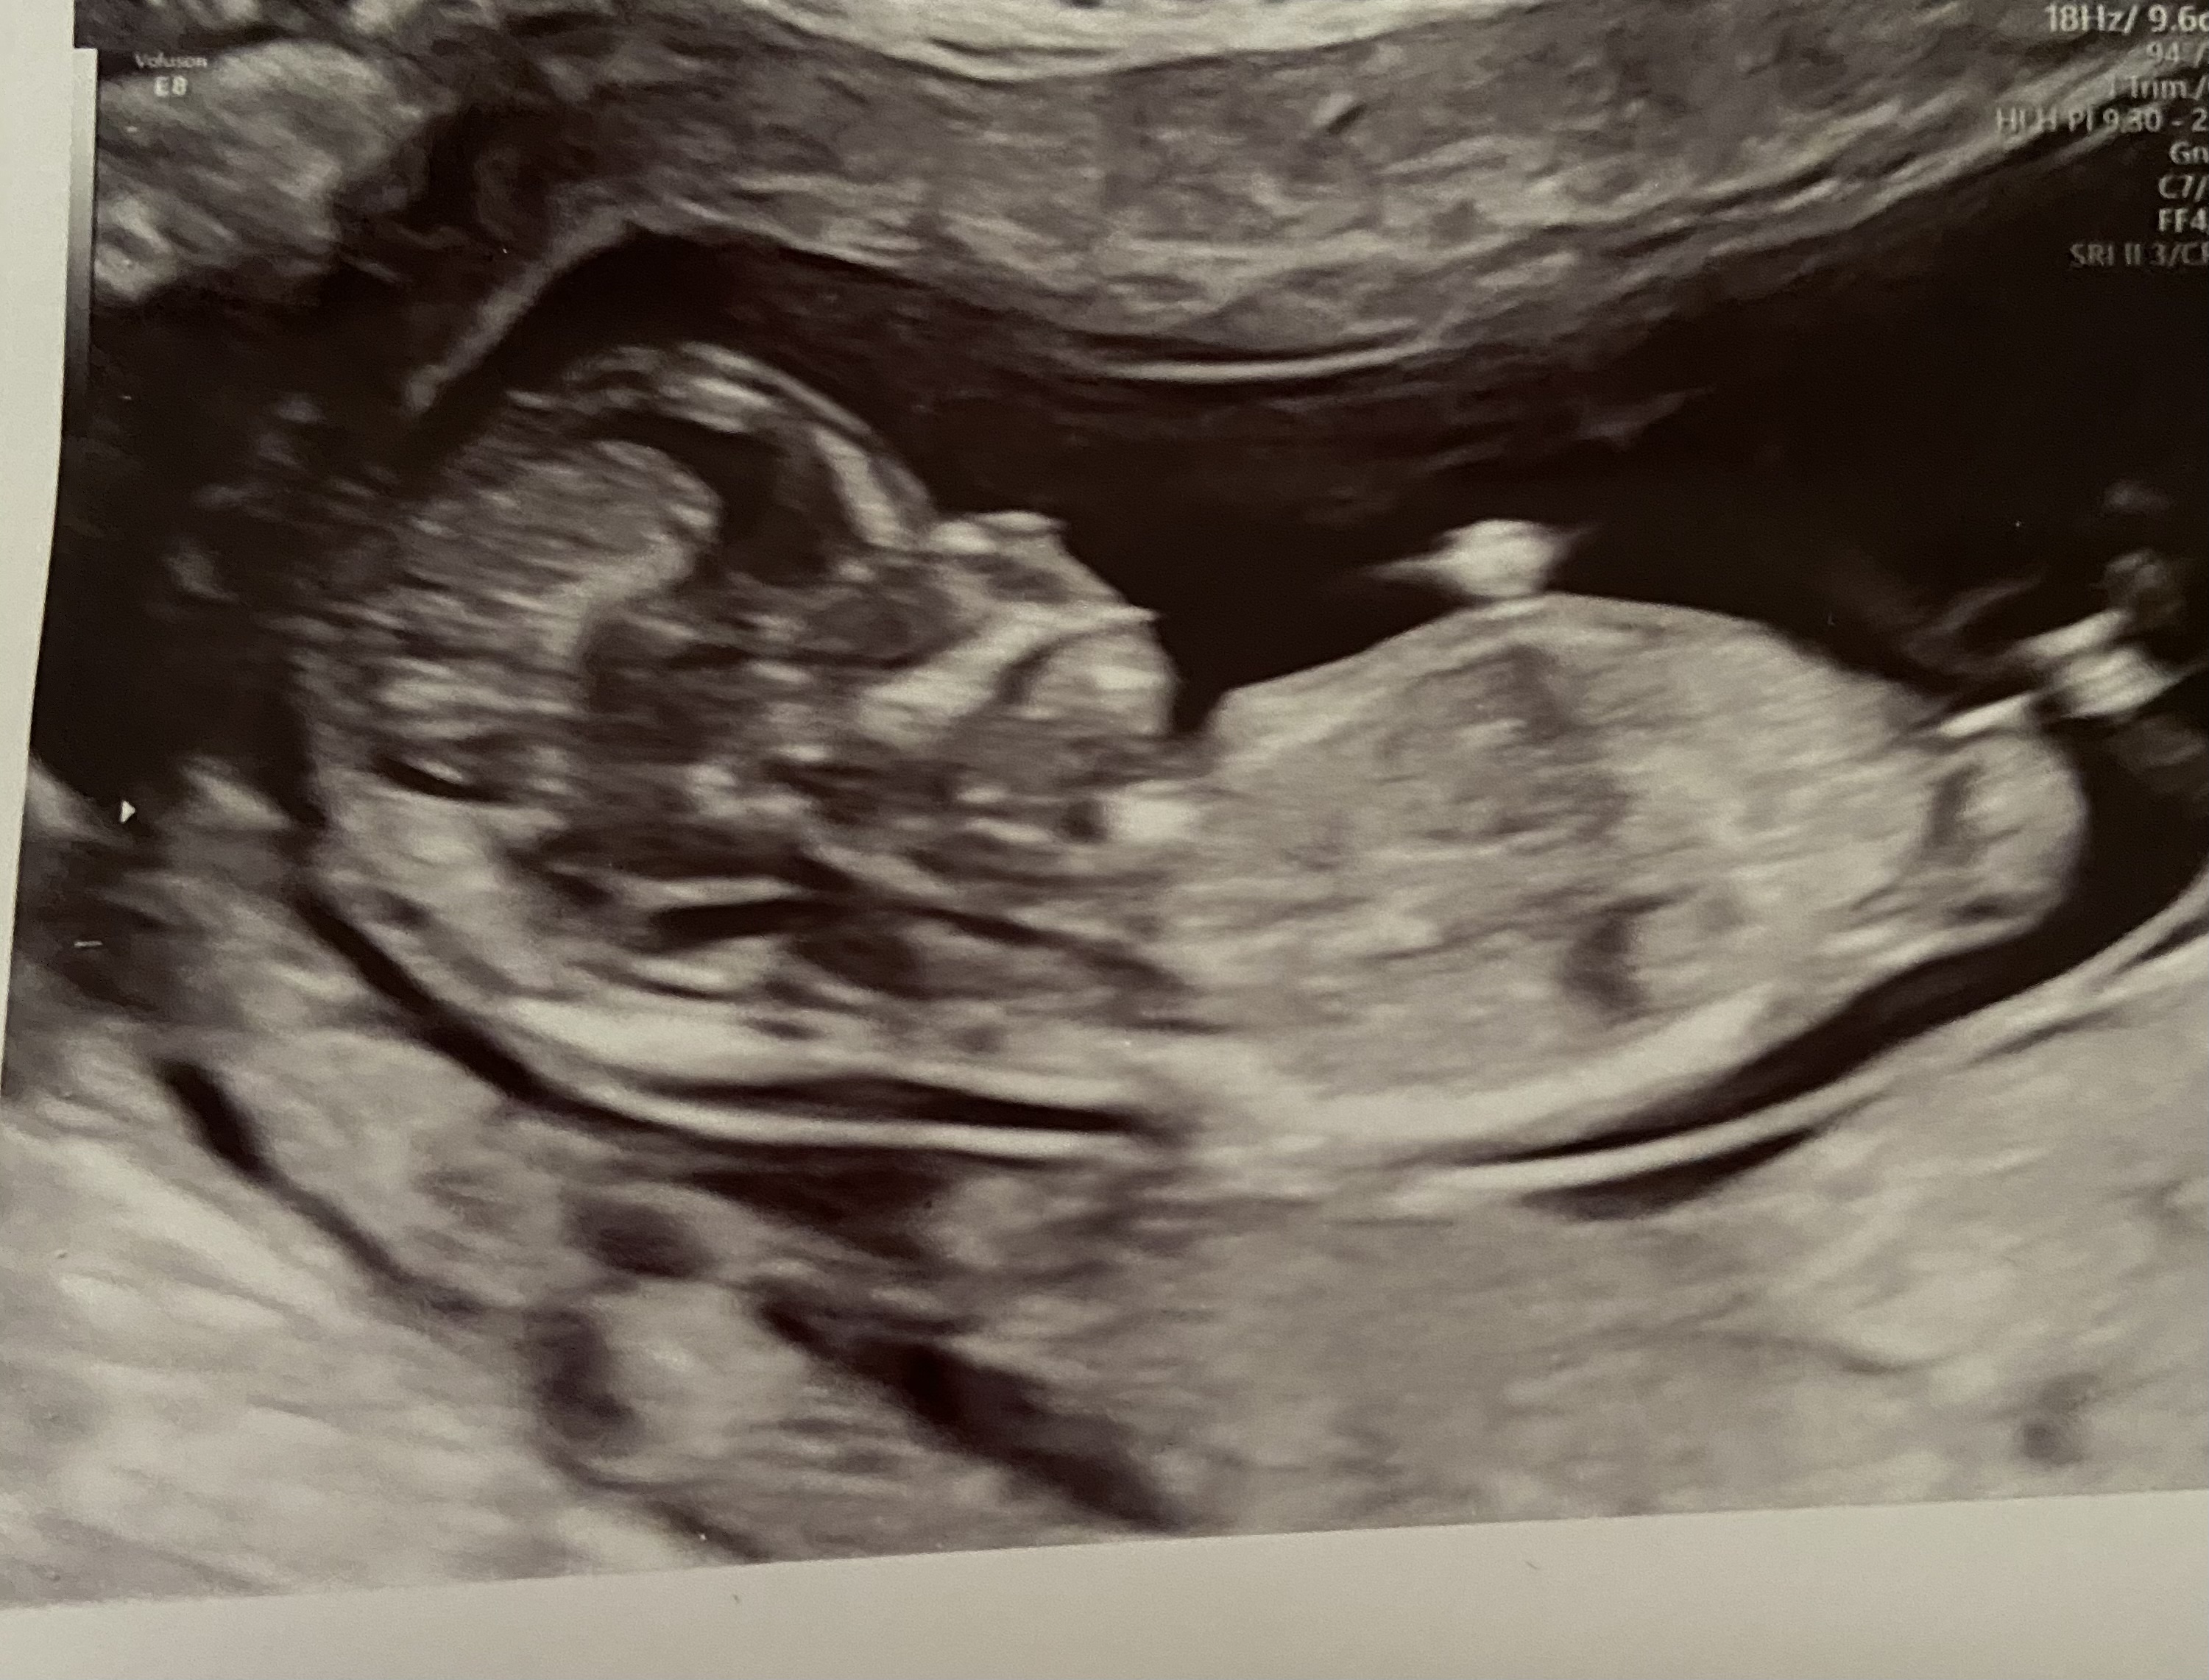

Tentative pink lean, but I'm not real sure to be honest. The top pic looks straight but the end is obscure, the bottom pic also looks straight but "busy". I think the bottom pic is a girl nub but the baby moved and made it look more stacked (the stacking is not in the right place to be real stacking) but it's just not something I can say with any level of certainty.